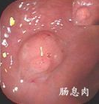

痔疮症状图片

直肠息肉早期症状